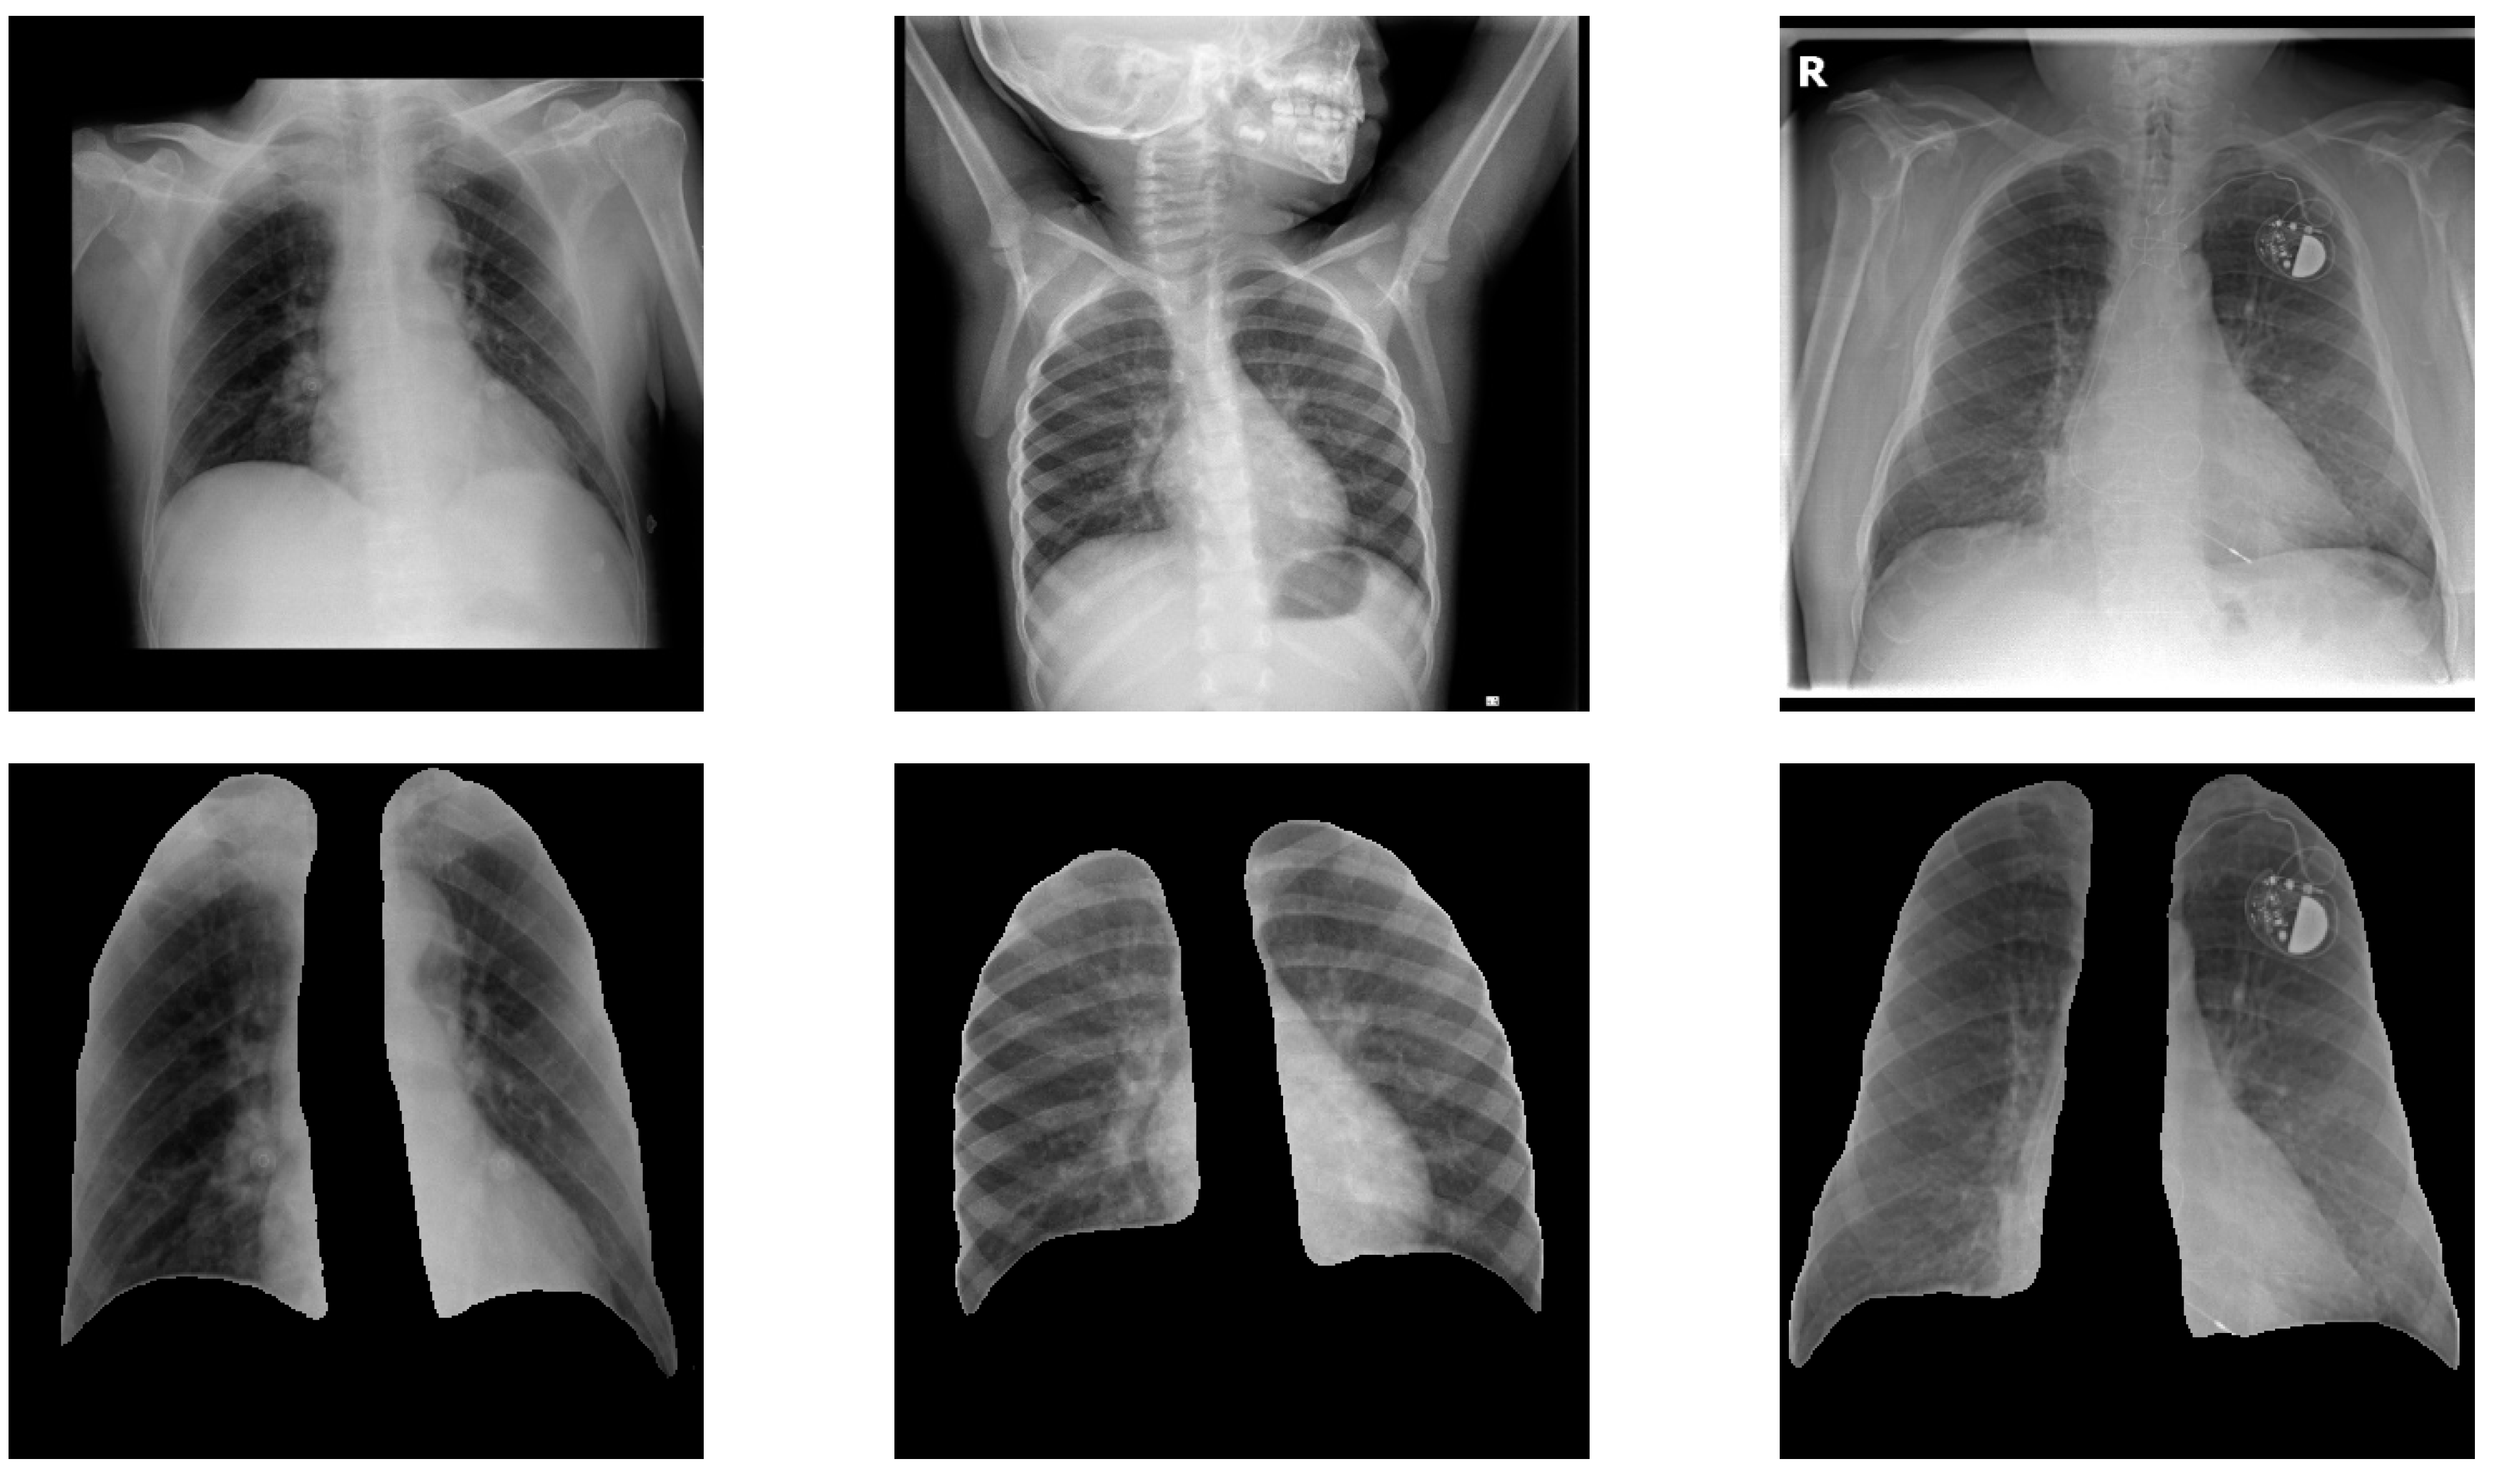

3.2.1. Lung Localization

3.2.2. Lung Segmentation